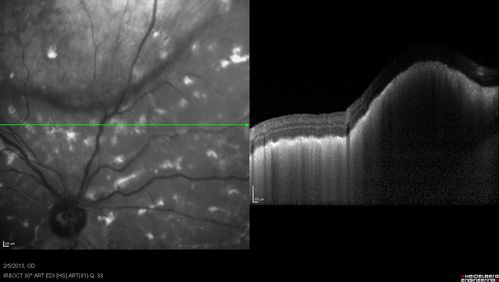

Primary Ocular Lymphoma - 020513 - SD OCT

Primary Ocular Lymphoma